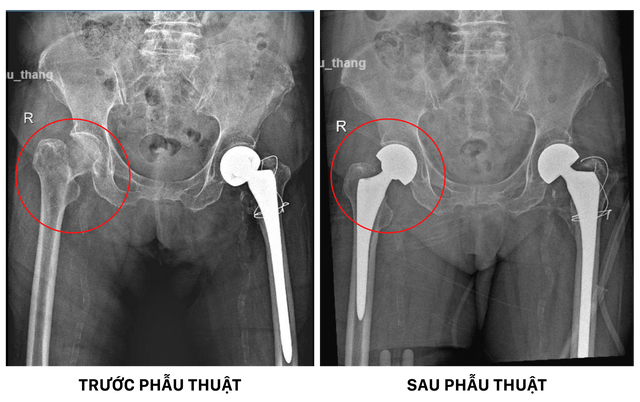

Tình trạng khớp háng phải trước và sau phẫu thuật thay khớp háng nhân tạo

Khi tình trạng đủ ổn định, ca phẫu thuật thay khớp háng bán phần được tiến hành ngay lập tức để tái lập khả năng vận động cho người bệnh. Ekip Chấn thương chỉnh hình gồm BS.CKI Sơn Tấn Ngọc và BS Lê Võ Vĩnh Khải tiếp cận vùng gãy và ghi nhận cổ xương đùi phải đã gãy hoàn toàn, di lệch xa vị trí ban đầu. Phần đầu xương bị hư hỏng được cắt bỏ, lòng ống tủy được làm sạch và chuẩn bị để đặt chuôi khớp nhân tạo không xi-măng.

Sau đó, các bác sĩ lắp khớp háng mới bằng vật liệu hiện đại được ưa chuộng trong các ca thay khớp háng cho người lớn tuổi gần đây. Đồng thời, căn chỉnh tại chỗ cho khớp đạt tầm vận động tự nhiên, hạn chế tối đa nguy cơ trật khớp. Cuối cùng, vùng mổ được rửa sạch, đặt dẫn lưu và khâu phục hồi theo đúng giải phẫu.